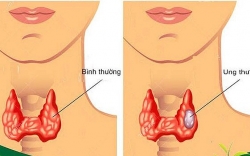

Ung thư tuyến giáp là gì? Nguyên nhân, triệu chứng và cách điều trị ung thư tuyến giáp

Nhắc đến bệnh ung thư tuyến giáp thì đa số mọi người đều hình dung được những biến chứng nguy hiểm của bệnh này, thậm chí nhiều người còn nghĩ “mắc ung thư thì chỉ ...